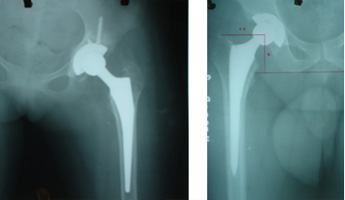

UNCEMENTED HIP REPLACEMENT

CEMENTED HIP REPLACEMENT